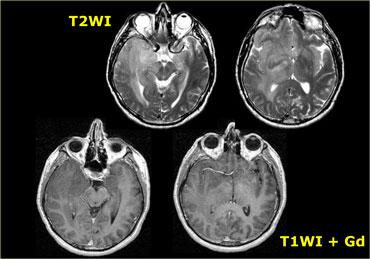

U thần kinh bao (Schwannoma) vùng góc cầu tiểu não với các đặc điểm điển hình của u ngoài trục (Chuỗi xung T2W)

Chuỗi xung T2W cho thấy một u thần kinh bao (schwannoma) nằm ở góc cầu tiểu não (CPA).

Trường hợp này minh họa rõ nét các dấu hiệu điển hình của u ngoài trục.

Có khe dịch não tủy (mũi tên vàng).

Các mạch máu dưới nhện chạy trên bề mặt não bị tổn thương đẩy lệch (mũi tên xanh lam).

Có chất xám nằm giữa tổn thương và chất trắng (mũi tên đỏ cong).

Khoang dưới nhện bị giãn rộng do sự phát triển của tổn thương ngoài trục có xu hướng đẩy lùi não.

Tất cả các dấu hiệu này cho thấy đây là một u ngoài trục điển hình.

Tại vùng góc cầu tiểu não, 90% các u ngoài trục là u thần kinh bao (schwannoma).